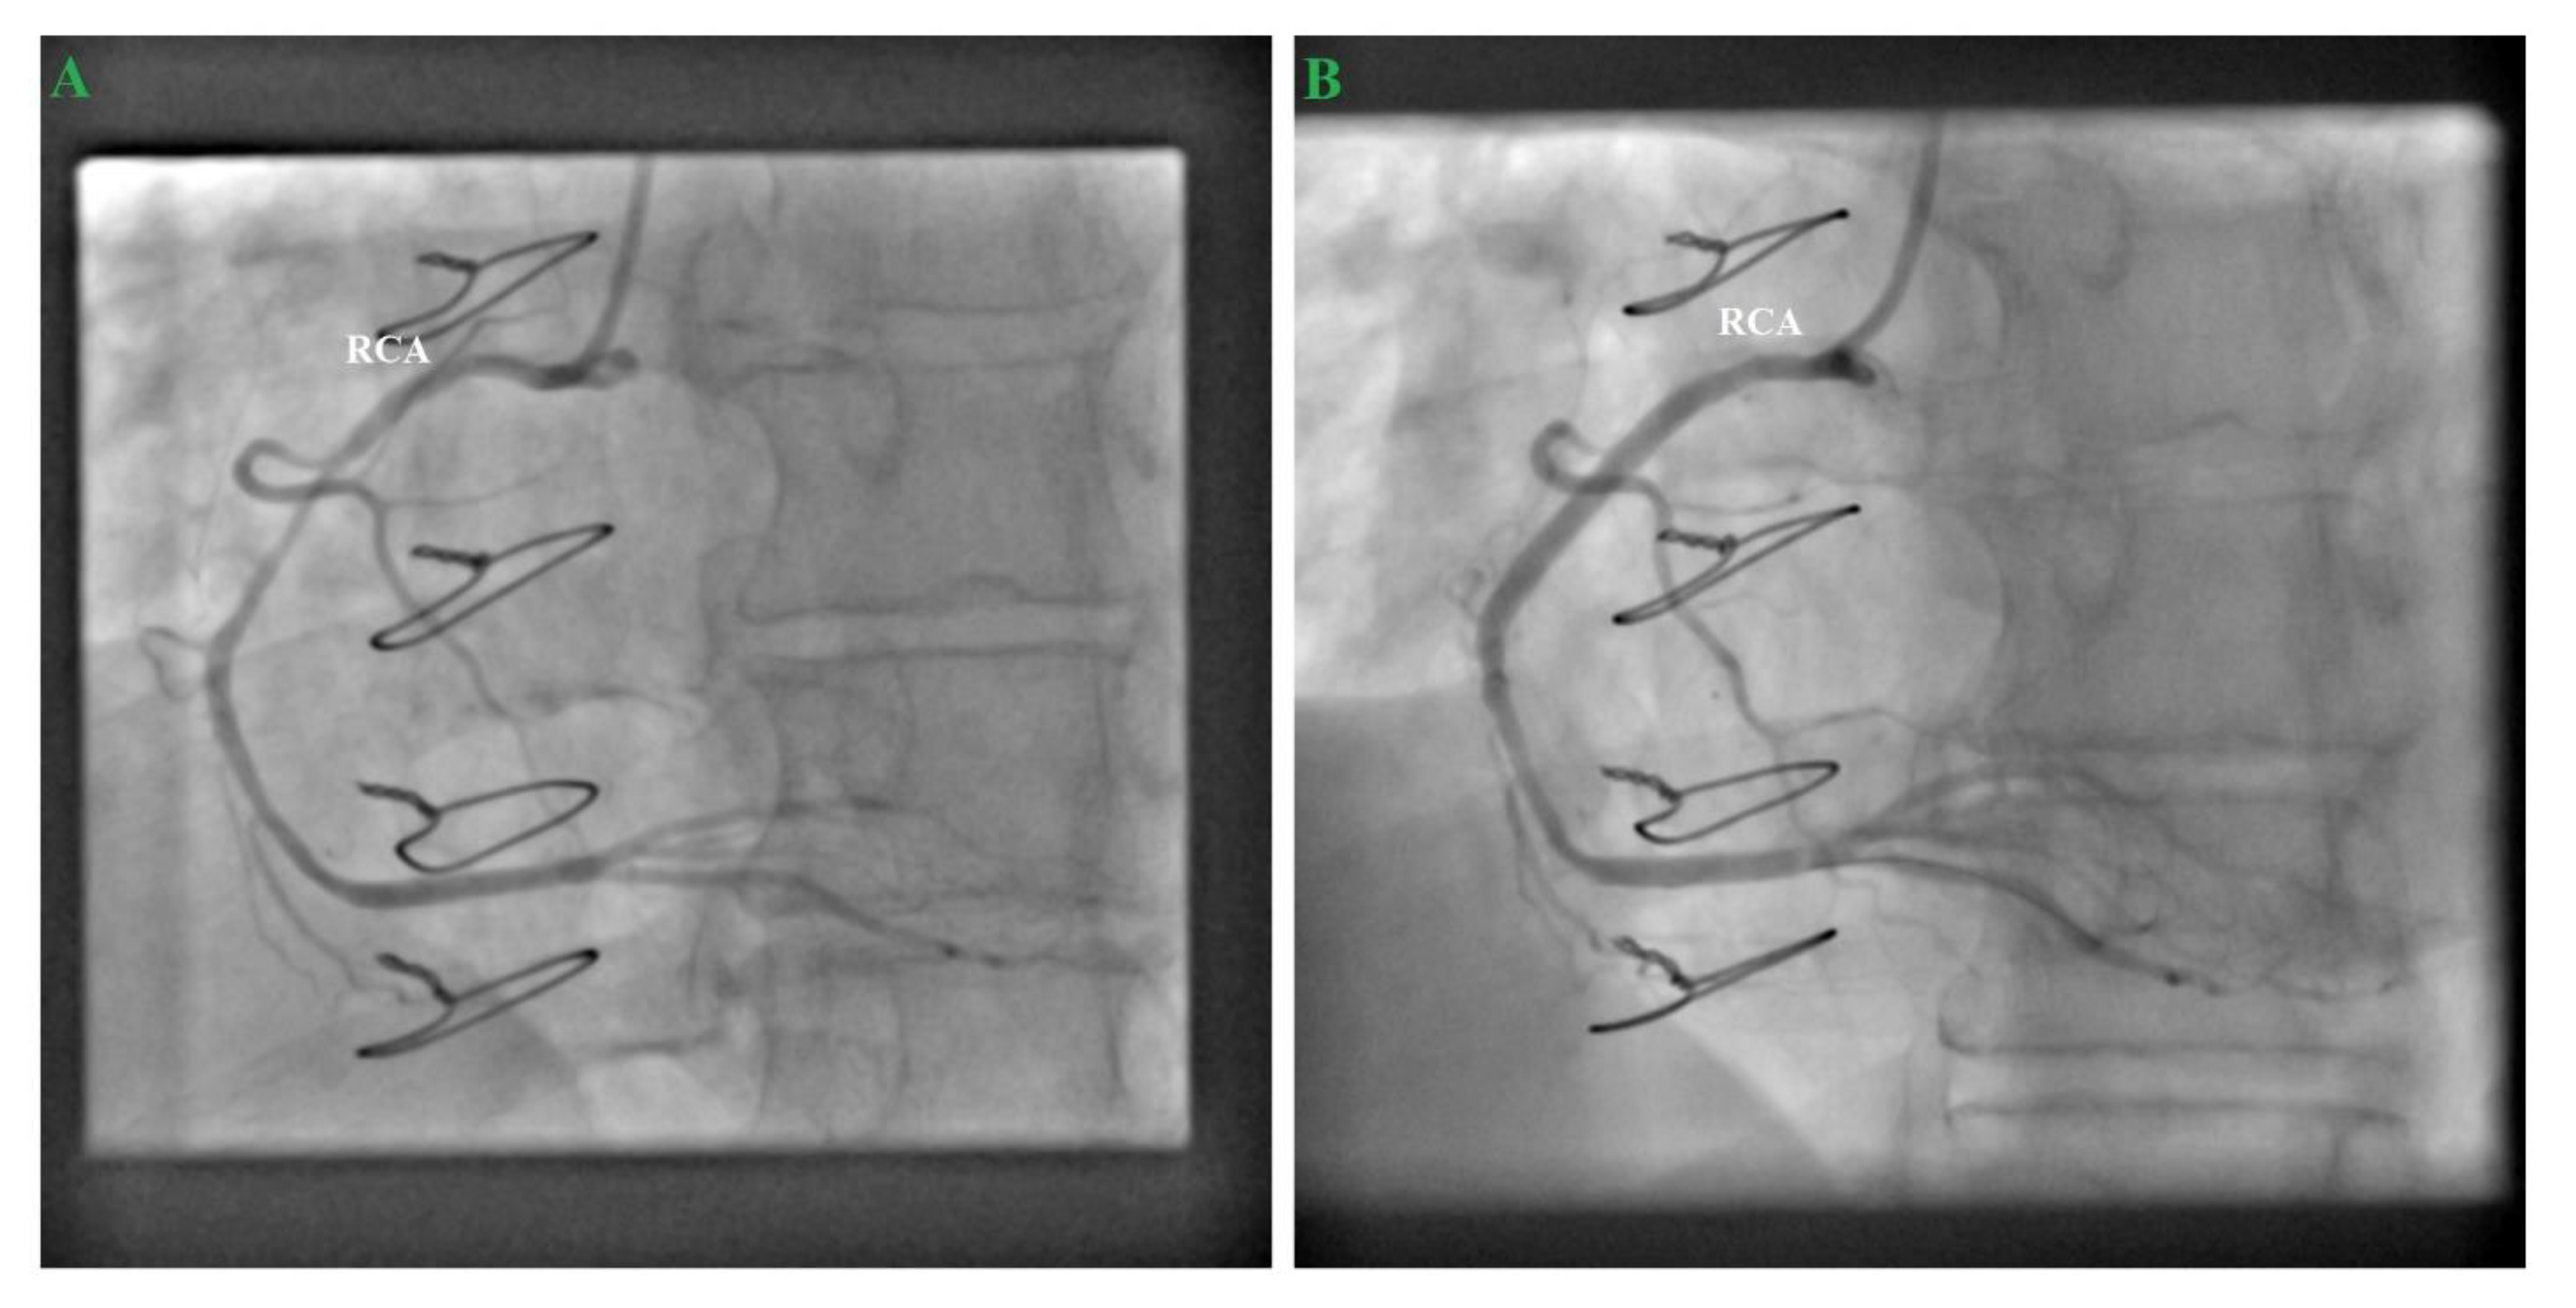

2. Case Report